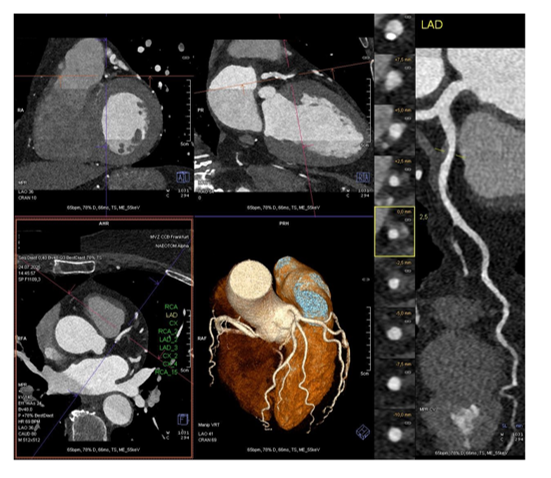

• Beschreibung von kalzifizierten, nicht-kalzifizierten und gemischten Plaques unter Verwendung von Rekonstruktion (Darstellung verschiedener Ebenen: axial, sagittal, koronal und multiplanar; s. Abbildung 1). Erwähnung von „High-Risk-Plaque“-Charakteristika wie positives Remodeling, „low attenuation plaques“, „spotty calcifications“ und „napkin ring sign“ (s. Abbildung 2).

kardiale-ct-multiplanare-rekonstruktion

© Giokoglu

Abb. 1: Multiplanare Rekonstruktion (axial, sagittal, koronal und „curved planar reconstruction” der LAD) und 3D-Visualisierung („cinematic rendering technique”). Rechts im Bild Beispiel eines positiven Remodeling der proximalen „curved“ LAD als Risikomerkmal, s. auch gelb umrandetes Querschnittsbild (Naeotom Alpha Photon-Counting-CT)